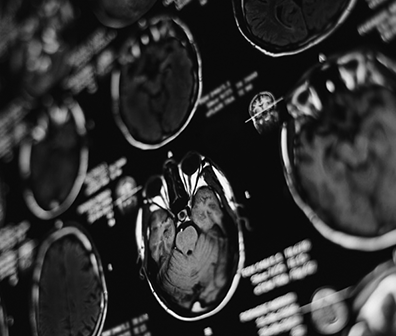

听神经瘤是颅内轴外肿瘤,起源于覆盖前庭或耳蜗神经的许旺细胞鞘。随着听神经瘤尺寸的增加,它们较终占据了桥小脑角的很大一部分。听神经瘤约占小脑桥脑角肿瘤的80%。其余20%主...

听神经瘤,也称为前庭神经鞘瘤,是一种少见的非癌性肿瘤。它们不会扩散(转移)到身体的其他部位。大脑并没有被声学肿瘤侵犯,只是肿瘤在扩大的同时推着大脑。听觉肿瘤占全部脑瘤...